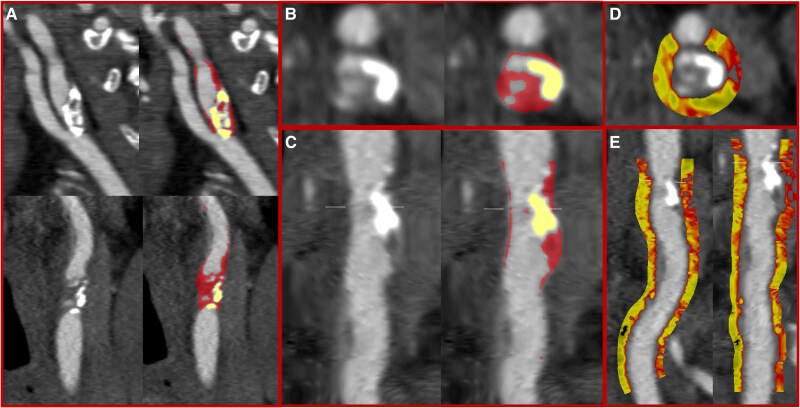

Methods and results: Carotid CT angiography was performed in 48 patients with acute ischaemic stroke or transient ischaemic attack within 21 days. Quantitative plaque assessment was performed in the proximal 6 cm of the internal and external carotid artery, distal 6 cm of the common carotid artery, and residual common carotid artery. Semi-automated quantification included assessment of non-calcified, calcified, low-attenuation, and total plaque, area and diameter stenosis, and peri-vascular adipose tissue attenuation. In 48 patients (mean age 71 ± 11 years, 67% male), 96 vessels were assessed with 30 (31%) identified as culprit vessels. Culprit internal carotid arteries had greater area [83 (65, 94) vs. 64 (55, 77)%] and diameter [56 (39, 74) vs. 32 (21, 48)%] stenosis and more non-calcified [563 (413, 965) vs. 428 (283 649) mm3, P = 0.04], low-attenuation [33.7 (6.9, 72.4) vs. 16.3 (3.35, 54.3) mm3, P = 0.01], and total [699 (455, 1057) vs. 492 (311, 809), P = 0.04] plaque. There was no difference in calcified plaque or peri-vascular adipose tissue attenuation between culprit and non-culprit internal carotid arteries. There were no differences in quantitative plaque or peri-vascular adipose tissue attenuation in the external carotid artery or common carotid artery.

Conclusion: Carotid atherosclerotic plaque characteristics are the principal features associated with culprit plaques with little or no demonstrable relationship with calcified plaque or increased peri-vascular adipose tissue attenuation.